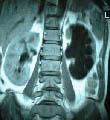

2.肾癌(又称肾细胞癌、肾透明细胞癌) 注意发病年龄及有无下述表现:①间歇性无痛性血尿、肾区钝痛,并可出现全身症状,包括低热、贫血、红细胞增多、高血压、高钙血症等。②肾区叩击痛,肾肿大,症状性精索静脉曲张及腹部肿物。③泌尿系X线平片及尿路造影:患肾影增大,肾盂、肾盏受压变形。膀胱镜检查可见患侧输尿管开口喷血。④放射性核素肾扫描:癌肿>3cm者出现放射性稀疏区。⑤肾动脉造影(对早期癌更具有诊断价值):显示出癌瘤的病理血管像,如向肾动脉内注入肾上腺素后再作选择性肾动脉造影,则病理血管像显示更为清晰;⑥B超和CT检查:对肾癌有较高的早期诊断价值。

4.肾母细胞瘤(胚胎瘤) 注意发病年龄(大多发生在幼儿,偶见于中青年)及有无下述表现:①以腹部肿物为第一症状,贫血、低热、高血压常见,但血尿少见。②尿路造影不显影或显示肾盂、肾盏变形移位,肾影增大,肿瘤区可见钙化影,输尿管可被肿瘤推向中线。③放射性核素肾扫描,显示患肾放射性缺损及稀疏。④肺、骨骼可有早期转移。⑤B超、CT或MRI检查。

其中,B超是筛查肾癌最合适的方法之一,可发现直径08cm的肾肿瘤。如果B超发现异常者,应进行CT检查,该方法可发现05cm以上的肿瘤,仍不能确诊者还要进行核磁共振检查。